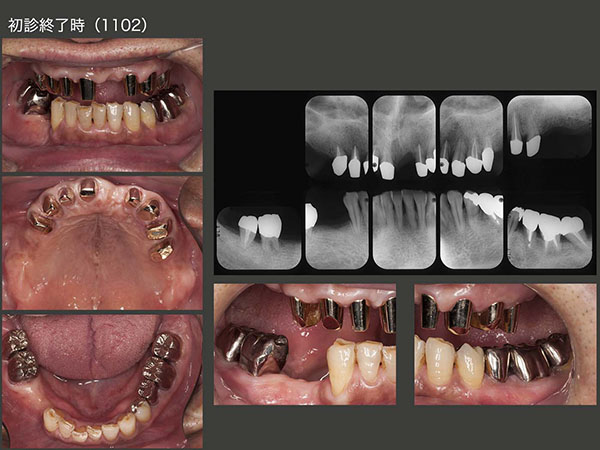

3.重度歯周病にコーヌス義歯で対応(1)

2012年2月初診,52歳男性.右下1および右上3の歯がグラグラするが主訴.歯周病がかなり進行しており,保存不可能な歯があるが,本人はどうしても歯を抜きたくないとのこと.まず,歯周基本治療を行い,右上3を抜髄し,自然挺出を開始した.

当院の環境に慣れてきたところで,保存不可能な歯の抜歯を行った.スライドにみられるように,歯石が根尖まで付着している.このような歯を放置すると,顎堤が吸収し,義歯の安定が得られなくなってしまう.

なお,抜歯を行うにあたって,2012年11月,即時義歯を装着した.上顎の口蓋を覆う義歯を装着したため,患者さんは違和感を強く訴えた.その後自然挺出を行った右上3および左下5に,歯周外科処置を施した.

2014年9月,初診終了時の状態.片側処理の可撤式義歯を合計3個装着した.支台歯の歯周ポケットは3mm以下に改善したが,予後が心配な歯であることに変わりはない.そこで,清掃性が良く,将来の変化に対応しやすいコーヌス義歯を採用することにした.左下も可撤式にしたかったが,経済的な負担も大きくなるので,左下5,6は,クラウンで連結固定した.下顎前歯は,ここで咬まないということを条件に,抜去した歯を単に接着剤(スーパーボンド)で隣在歯と固定した.また,みるからに咬合力が強いと思われることから,意識して咬み過ぎないように,さらに日中の咬みしめ(TCH)に特に注意するよう指導した.